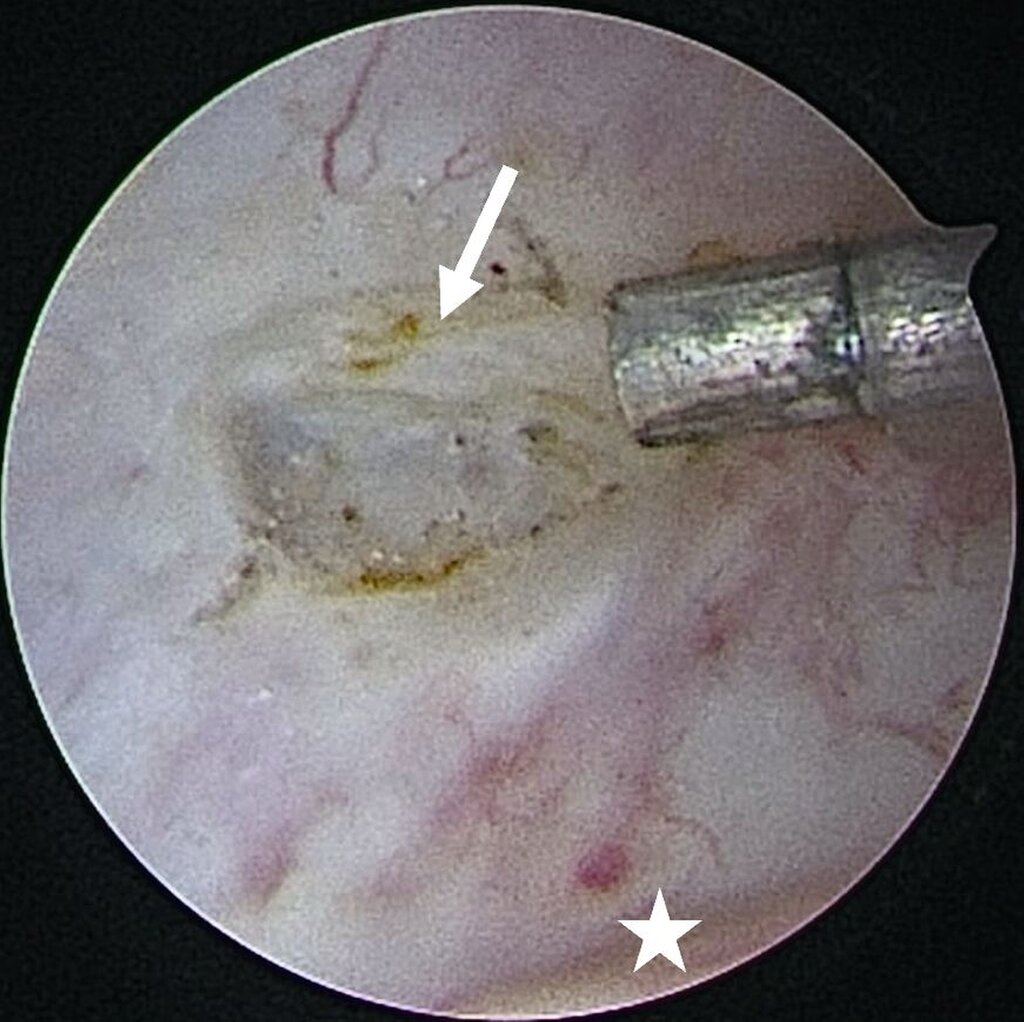

Eine Entzündung im Bereich der Gelenkkapsel (Synovitis) stellt eine häufige Ursache für arthrogen bedingte Beschwerden dar [Mercuri et al., 2025]. Neben der Darstellung des Gelenks und der Behandlung von Pathologien beruht ein positiver Effekt der Arthroskopie auf der Lavage des Gelenks. Dadurch können zum Beispiel proinflammatorische Mediatoren entfernt und intraartikuläre Adhäsionen gelöst werden [Soni, 2019]. Abbildung 2 zeigt die intraoperativen Befunde von zwei Patienten. Es wird jeweils der Übergang zwischen dem hinteren Aufhängungsband und der pars posterior des Discus articularis dargestellt.

Im Rahmen einer Level-II-Arthroskopie (Abbildung 8) in Vollnarkose konnte der Gelenkkörper nach Zerkleinerung durch Coblation über einen Arbeitskanal vollständig entfernt werden. Die histologische Aufarbeitung ergab hyalinen Knorpel mit (sklerosiertem) Bindegewebe. Der Eingriff verlief komplikationslos; postoperativ zeigte sich unmittelbar eine regelrechte Okklusion. Die Schmerzen waren am ersten postoperativen Tag bereits vollständig regredient.